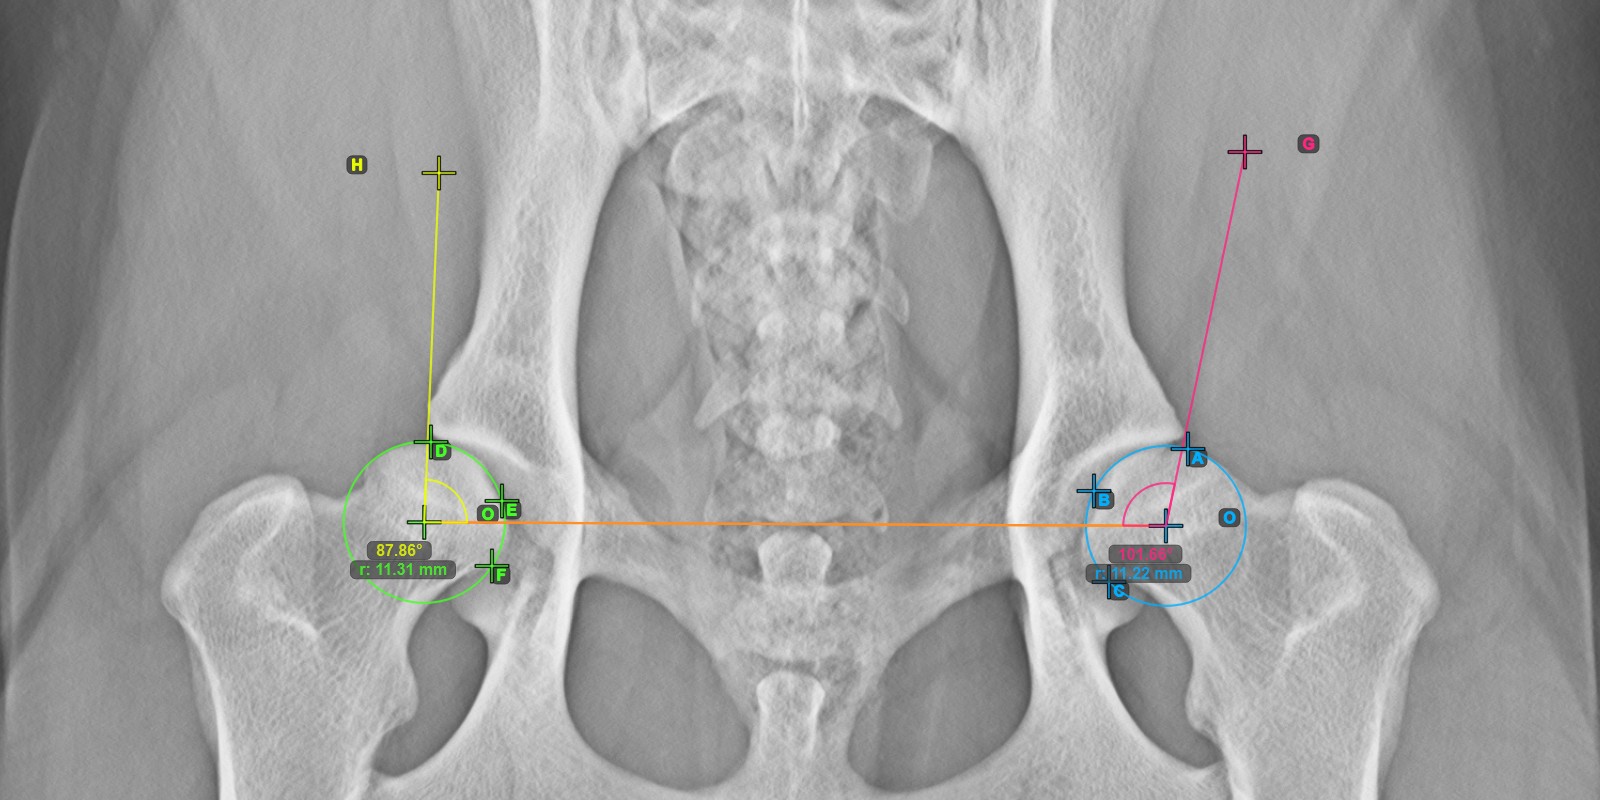

A lenti kép a vonal tipikus elhelyezkedését és a kiszámított Norberg szög mérését ábrázolja.

Számítsa ki a jobb Norberg szög mérését azáltal, hogy egy vonalat jelöl a jobb Acetabulum csont hatékony szélén, ezzel befejezve az egész komplex mérést.

Jelöljön meg egy pontot a jobb Caput Femoris közelében, és húzza azt a jobb Acetabulum csont hatékony széle mentén, kialakítva a jobb Norberg szög végoldalát.

A megrajzolt vonalnak tangensnek kell lennie a jobb Acetabulum csont hatékony széléhez. A szög értéke és íve automatikusan kiszámításra kerül.